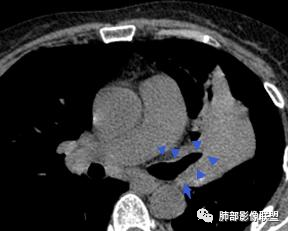

左肺团块影,形态不规则,其内见充气支气管征,增强扫描明显强化,其内见液化坏死区。下叶基底段见斑点状密度增高影。双肺门见斑点状钙化影。疾病谱有结核,增强除外了。肺癌和淋巴瘤鉴别。

整个上叶尖后段阻塞性肺不张的表现,从强化来看没有异常结节状或肿块样强化,肿块内部点状钙化、纵隔多发小淋巴结、下叶背段有树芽征,整体来看支持肺结核,让人不放心的是最后一幅冠状位重建的图像尖后段支气管堵了,而且有轻度的隆起,所以很难除外粘液表皮样癌(女性,鳞癌可能性小),如果是我写报告肯定会建议纤支镜检查

左上叶实变不张,膨胀生长,上叶开口阻塞?,病灶内支气管扩张,明显延迟强化,内见低密度灶及点状钙化,周边见小叶间隔增厚丶结节,右斜裂结节

左肺上叶软组织肿块,密度不均匀,边界清晰,不均匀强化伴坏死,支气管走行僵直

中年女性,咳嗽咳痰4月,加重半月。偶发热,肿瘤指标升高。病变主要位于左肺上叶后部,实变,病灶大部边缘平直、局部膨隆,邻近叶间裂局部向后膨隆,病变密度整体较均匀,见小斑片状低密度区及点状钙化影;左肺上叶舌段支气管可疑截断,病灶内支气管走形迂曲变形、不规则狭窄扩张、部分支气管内粘液栓形成,可见局部扩张支气管似小空洞相连,病灶内血管走形自然;糊墙。病灶前缘小叶间隔增厚,平滑;左肺下叶支气管管壁增厚,见部分树芽征及腺泡结节,边缘不清。纵膈及双肺门部分淋巴结钙化,隆突下淋巴结增大;未见胸腔积液。1.左肺上叶病灶倾向于恶性肿瘤,腺癌可能,排除粘液腺癌;2.左肺下叶少许炎症;

树芽征、小叶间隔增厚,淋巴结, 内部血管走形自然

分析:支气管粘液栓、支气管堵塞处萎缩、钙化,支气管通畅处部分扩张,树芽征——提示结核。

病灶膨隆明显,支气管堵塞,附近壁增厚,是否需要警惕恶性?

腺癌?近端支气管壁增厚,病灶区占位效应明显,小叶间隔增厚,血管走形自然,不能排除  。

2.左肺上叶大片实变影,密度不均,体积轻度增大,注意轻到中度强化及血管影未见破坏、未见坏死空洞……病灶更符合炎症,而不大支持干酪性结核及肺鳞癌等,后两者的破坏能力是比较强的。

3.支气管阻塞,沿途可见钙化及液性潴留……更符合支气管内膜结核。